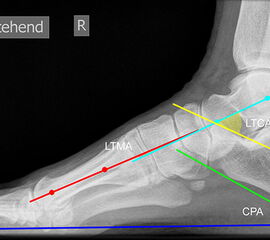

Achsen auf der lateralen Aufnahme

Die Grundlinie (blau) ist definiert durch den tiefsten Punkt der Sesambeine und den tiefsten Punkt des Kalkaneus.

CPA (Calcaneal pitch angle): Der Kalkaneus Inklinationswinkel liegt zwischen der Grundlinie (blau) und der plantaren Begrenzung des Kalkaneus (grün) (Norm 20,8 ± 4,1° 11, 15-39° (Zwipp 2014)).

LTCA (Lateral talocalcaneal angle): Der laterale talokalkaneare Winkel liegt wird gebildet aus der Talusachse (türkis) und einer Verbindungslinie zwischen dem Oberrand des Proc. ant. Calcanei und der dorsalen Begrenzung des Kalkaneus (gelb). (Norm: 33° Range 25-45°) 1213).

LTMA (Lateral talometatarsal angle, Syn. Meary’s angle): Der laterale talometatarsale Winkel wird gebildet aus der Achse des Os metatarsale I (rot) und der Achse des Talus (türkis). (Norm: 7,1 ± 10,8 11).